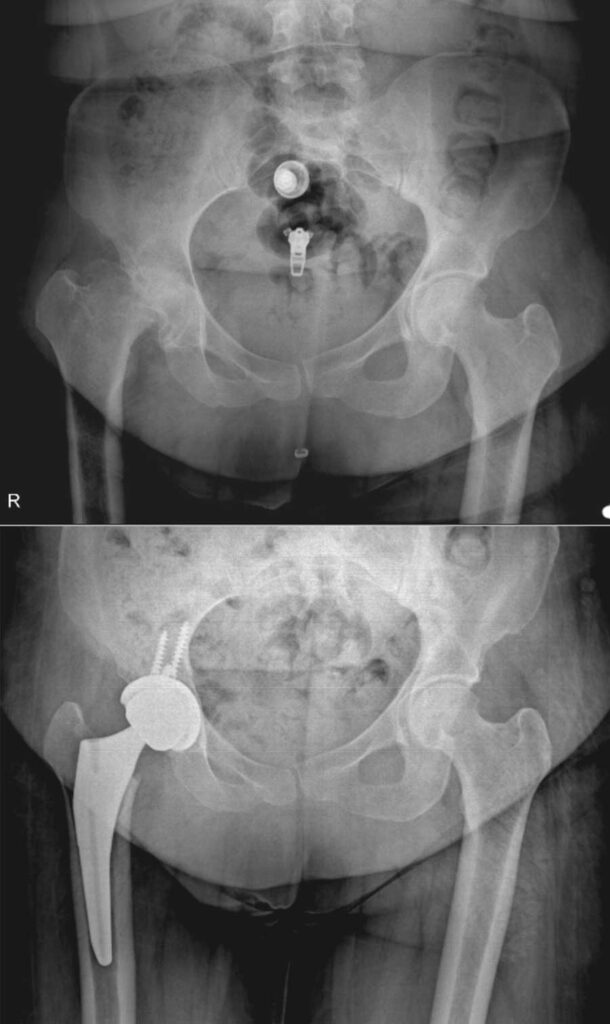

عکس تعویض مفصل لگن

برای آشنایی با تصاویر واقعی رادیوگرافی لگن قبل و بعد از جراحی، عکس تعویض مفصل لگن چند بیمار در زیر وجود دارد. با کلیک بر روی هر کدام از آنها تصویر بزرگتر و کامل را خواهید دید.